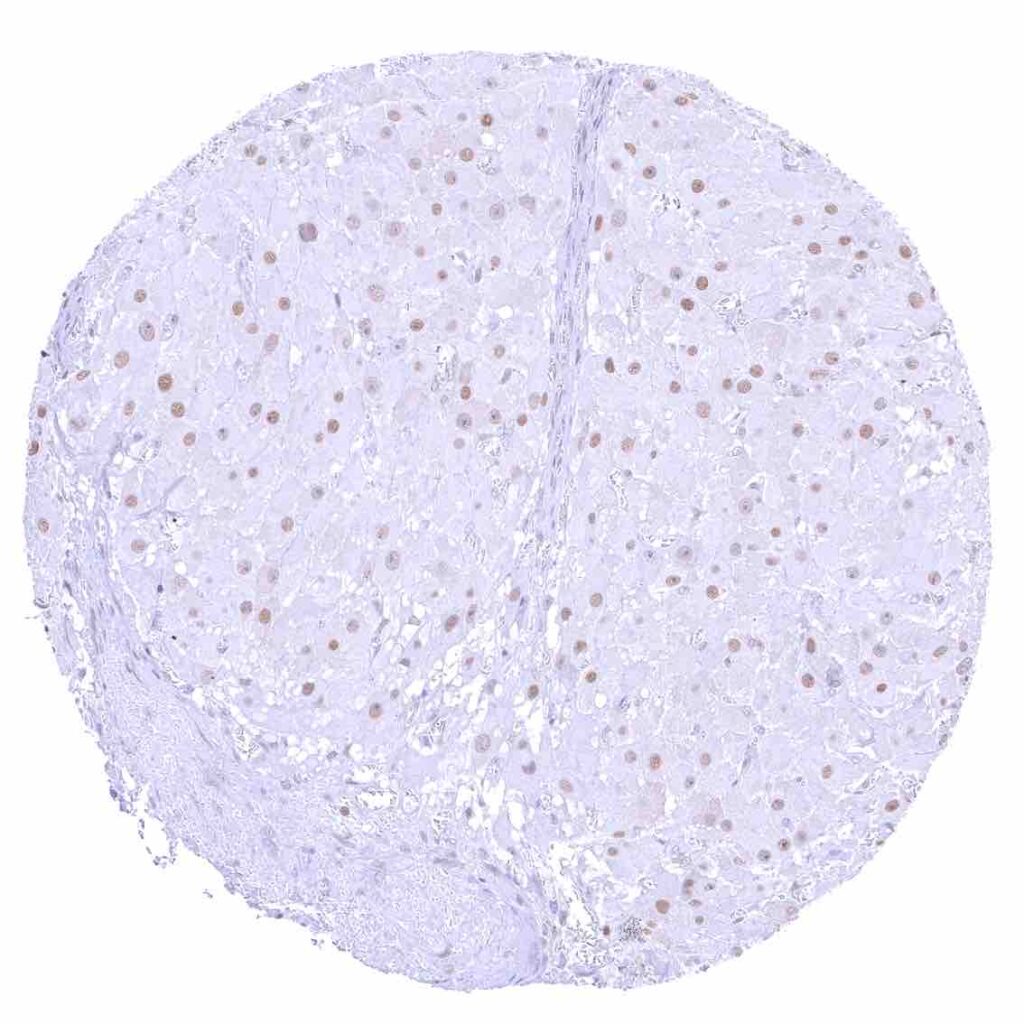

Liver – p27 staining is rare or absent in hepatocytes.